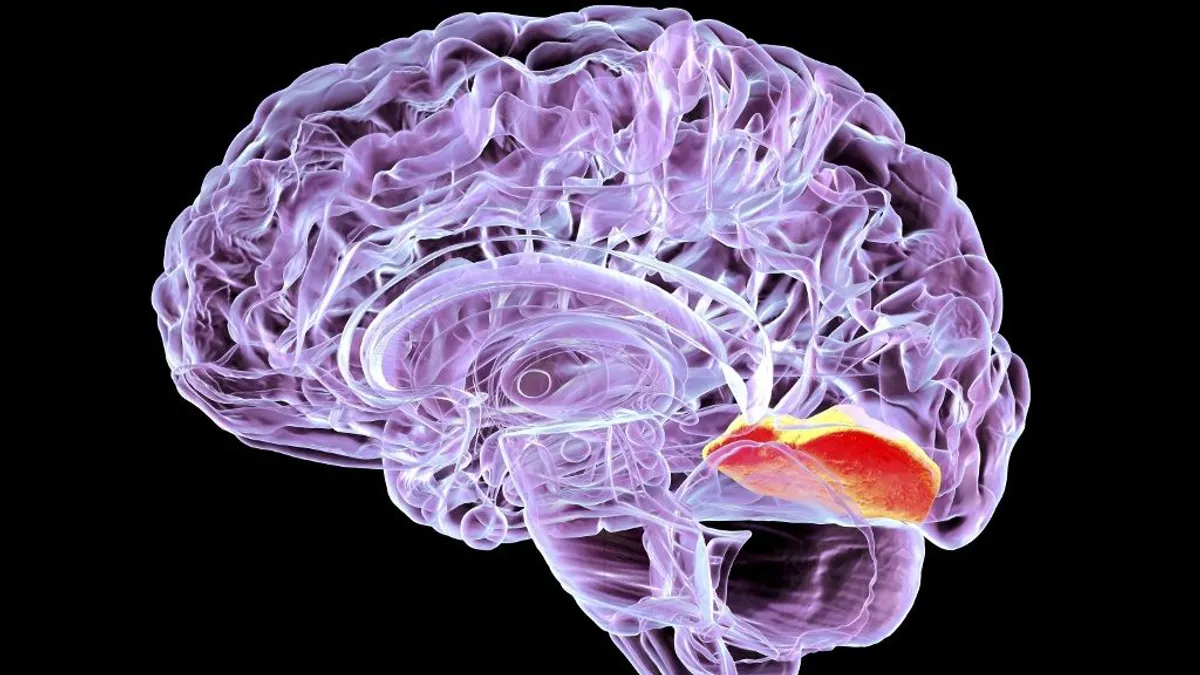

Mi történik, ha megfertőződünk ezzel az új, veszélyes betegséggel, ami embert és kutyát is fenyeget? – Itt a válasz

Egyre többször fordul elő hazánkban is a galandféreg okozta echinococcosis, ami embert és kutyát is megbetegíthet, hívta fel a figyelmet a Semmelweis Egyetem. A témával kapcsolatos kérdésekre dr. Kardics Kinga, a Semmelweis Egyetem Gyermekgyógyászati Klinika infektológiai osztályának szakorvosa válaszolt.

![]() blikk.hu

A Semmelweis Egyetem figyelmeztet: halálos féreggel fertőzhetnek a kutyák

Hazánkban is mind gyakrabban fordul elő az állatról emberre terjedő, galandféreg terjesztette echinococcosis. A fertőzést aranysakálok, rókák, sőt, kutyák is terjesztik.